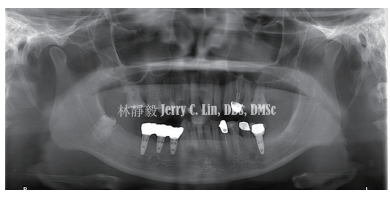

严重种植体周围炎的处理(二)——林静毅医师